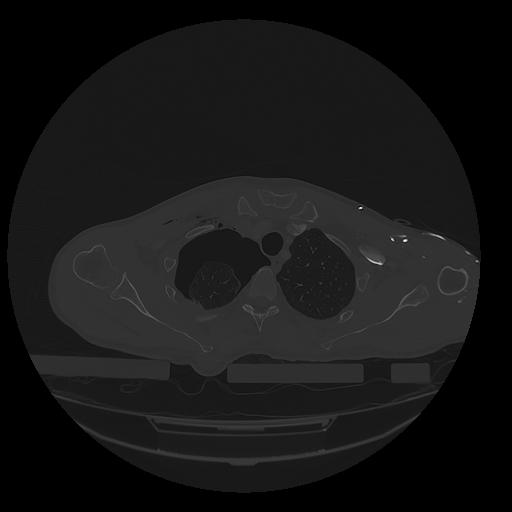

31 PULMON,CE,Vol,1.0,PULMON,,